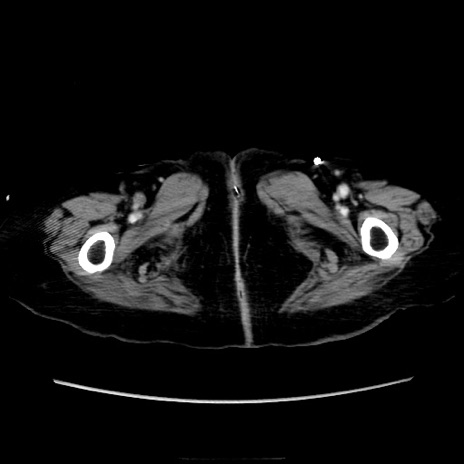

症例40(横断像)

横断像